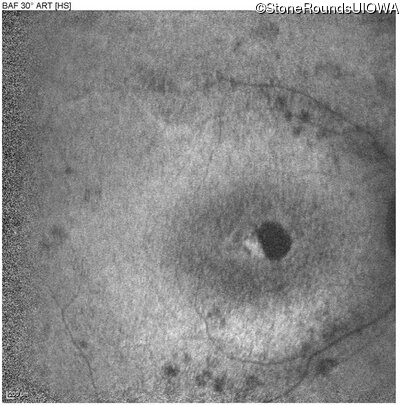

Blue Autofluorescence - Right - 5/180

Exemplar